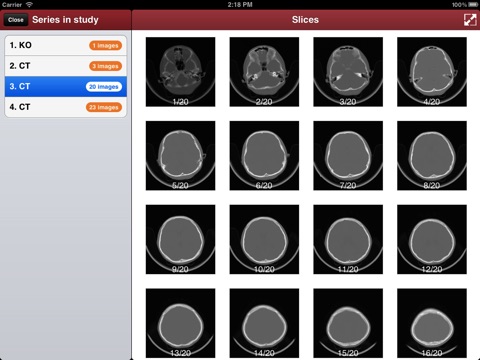

"DicomBox" is a DICOM software for iOS: DICOM is the digital standard for storing and transferring medical images. DicomBox allows downloading and manipulating series of images directly on your iOS device. DicomBox is capable of displaying images from all imaging modalities in their native standard DICOM format used by the medical/scientific industry. DicomBox is a fully DICOM-compliant listener that can receive images from any DICOM imaging device through WiFi/3G networks.